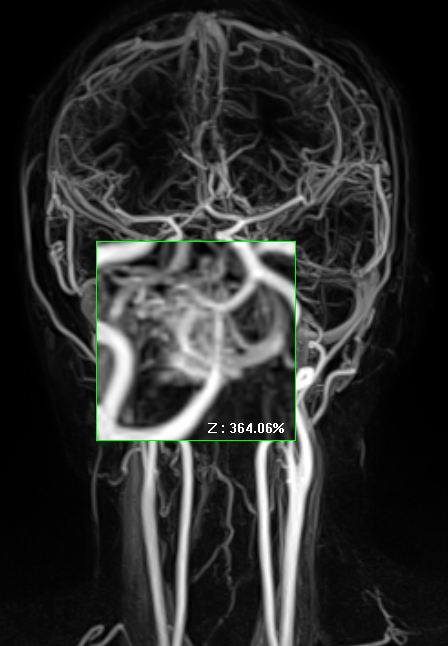

AVM은 중심부에 동맥과 정맥이 뒤얽힌 혈관누두를 형성하며, 영양동맥의 근육층은 약하고 배출정맥은 지속적인 고속 혈류로 확장되어 있는 것이 특징이다.

조영증강 CT나 CTA(CT angiography)을 시행하면 “뒤엉킨 벌레뭉치(bag of worms)” 같은 특징적 조영 패턴 나타난다.